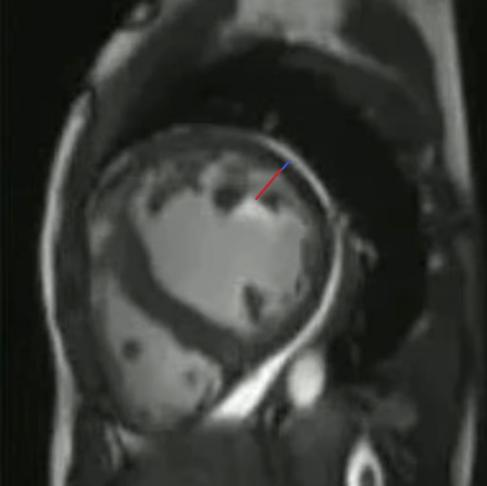

图片说明:LVNC患者,左室短轴平面,左心室非致密化心肌(红线)与致密化心肌(蓝线)厚度之比>2.3。

CMR的电影序列(cine CMR)能动态显示左心室的结构,最典型的表现就是左心室壁出现大量增粗、交错排列的肌小梁,尤其是在左室心尖部、侧壁下1/3和下壁区域。这些肌小梁之间是深而宽的隐窝,在舒张期和收缩期都能清晰看到,与心室腔直接连通。诊断的核心指标是:舒张末期非致密化心肌层厚度与致密化心肌层厚度的比值>2.3,这是区分正常变异和病理性致密化不全的重要界限。部分患者的肌小梁甚至会呈“鸟巢状”或“蜘蛛网样”分布,让左心室内壁看起来像粗糙的海绵。